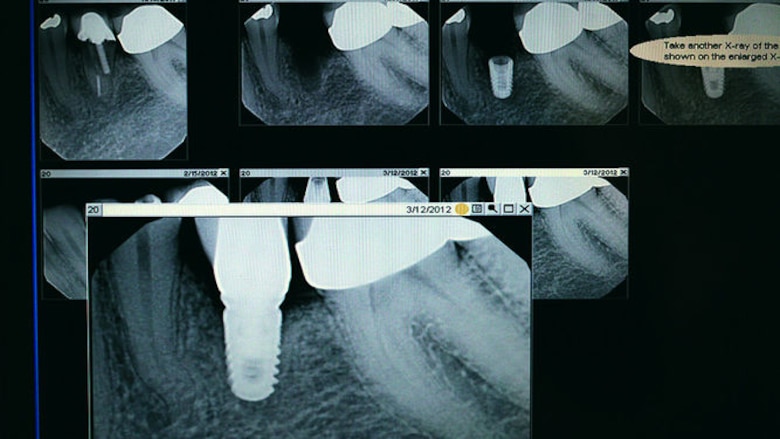

Desde hace más de siete años Gittens ha trabajado con implantes de titanio para aplicaciones del hueso. Esto incluye implantes dentales y ortopédicos, como los de reemplazo de cadera o de espina dorsal.

Cuando los implantes dentales se introdujeron al mercado, se aplicaban a pacientes relativamente jóvenes, pero las tasas de éxito no eran muy altas, describe. A medida que se ha estudiado más sobre la superficie de los implantes, se ha comprendido que es posible modificar las propiedades del material usado para mejorar su interacción con el organismo, explica.